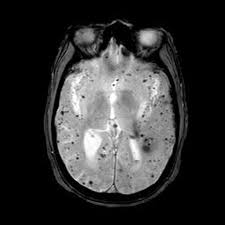

Microbleeds are very small spots left by tiny leaks of blood in the brain. They are not active bleeds. Instead, they are leftovers. The blood breaks down and leaves iron-rich pigments called hemosiderin behind. On special MRI scans, these spots look dark. Radiologists call them cerebral microbleeds or CMBs. They are usually under 5 mm in size. The fact they are small can be misleading. Small does not always mean harmless. How many there are and where they sit matters. The term is an imaging label. It tells doctors that a tiny vessel in the brain once leaked blood.

Doctors use MRI to see microbleeds. A sequence called susceptibility-weighted imaging (SWI) or T2* picks them up best. These scans are more sensitive than older MRI types. Higher magnetic field strength and better image settings reveal more spots. That means a scan with better technique may show microbleeds that another scan missed. This is important when comparing scans over time. Radiologists count and map the spots. They also note whether the microbleeds are deep or near the brain surface. The imaging details help doctors guess the likely cause and possible risk.

Two main disease types cause most microbleeds. One is hypertensive small vessel disease. This is linked to long-standing high blood pressure. It tends to cause microbleeds deep in the brain. The other is cerebral amyloid angiopathy. That involves protein build-up in vessel walls. It causes microbleeds near the brain surface, in lobar regions. Other causes include trauma, blood disorders, and rare genetic conditions. Age is a big factor. The older a person is, the more likely microbleeds will show up on scans. Clues from the MRI help doctors pick the most likely cause.

Microbleeds can show up in different brain zones. Deep microbleeds appear in the basal ganglia, thalamus, brainstem, or cerebellum. These deep spots are often linked to high blood pressure. Lobar microbleeds sit in the outer brain cortex and nearby white matter. Lobar spots are commonly tied to amyloid angiopathy, especially in older adults. The pattern matters. A deep pattern suggests one cause. A lobar pattern suggests another. Doctors use the pattern to guide decisions about treatment and future risk. Maps of microbleed locations help with clinical judgment.